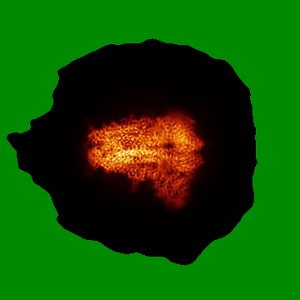

Structure of SARS-CoV-2 Spike Protein with Engineered x3 Disulfide (x3(D427C, V987C) and single Arg S1/S2 cleavage site), incubated in Low pH after 40-Day Storage in PBS, Locked-2 Conformation

Single-particle2.9 Å